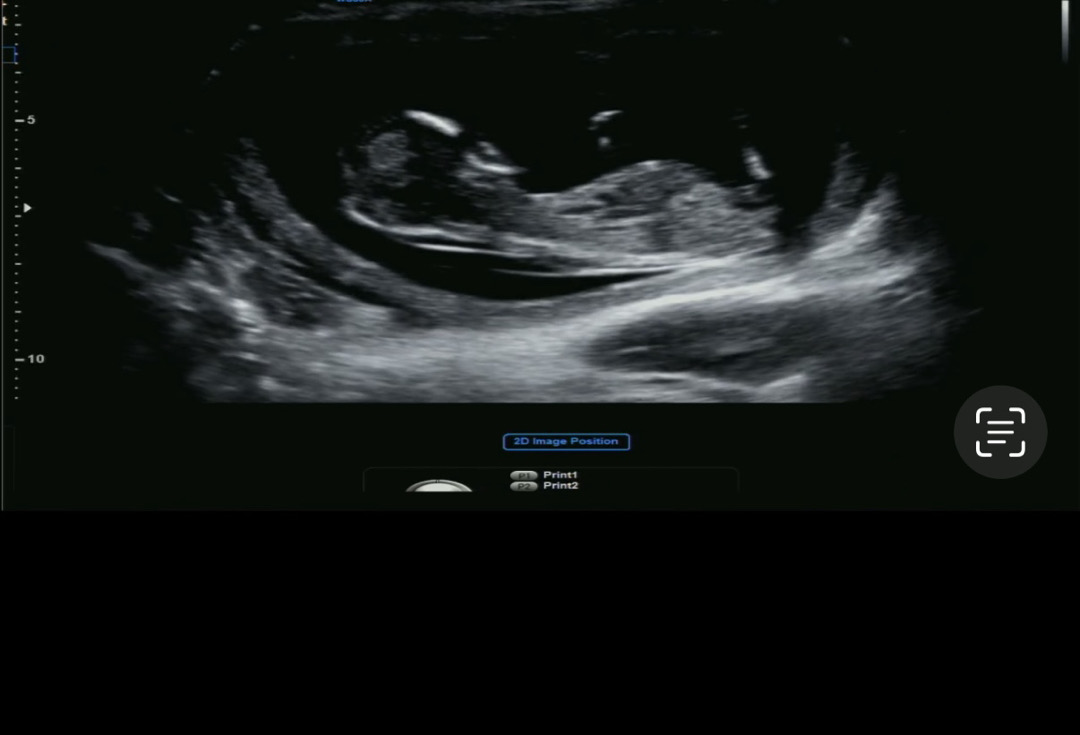

12주4일 각도법 문의드립니동🥹💛

12주4일 1차 기형아 검사 초음파 입니당! 각도법 고수님들 한번만 봐주세요🥹💗w